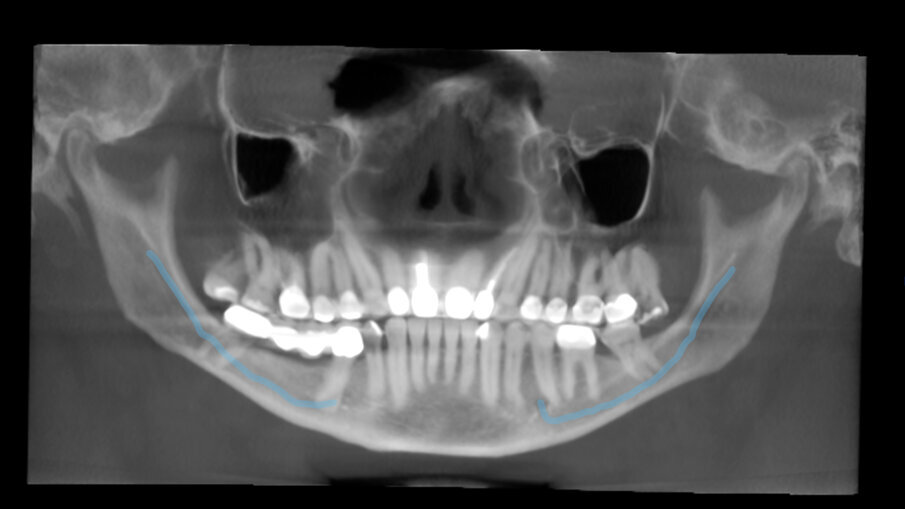

Treći slučaj naglašava veštačku inteligenciju ugrađenu u DTX Studio Clinic, čija je jedna karakteristika automatsko praćenje mandibularnog kanala. U ovom slučaju, to je bilo veoma korisno imati. Pacijent je bolovao od ireverzibilnog pulpitisa trećeg molara donje vilice. Želeo je da sačuva zub po svaku cenu, jer nije želeo da ima implantat (molar je bio potporni zub za most). Rendgenski snimak je pokazao da se koreni molara preklapaju sa mandibularnim kanalom (Sl. 12).

Napravljen je 3D radiograf, a na ovome je softver pratio mandibularni kanal koji se preklapa sa molarom u panoramskom prikazu. Endodontski režim softvera je otkrio da kanal zaobilazi bukalni deo, blago dodirujući meziobukalni kanal (Sl. 13–15). Na rendgenskom snimku odmah nakon terapije kanala korena, urađene kroz krunicu, uočena je potpuna obturacija svih kanala (Sl. 16).

Sl. 12: Rendgen snimak pre operacije, koji pokazuje blizak odnos između mandibularnog kanala i molara

Sl. 13: Praćenje putanje mandibularnog kanala

Sl. 14: Endodontski režim DTX Studio Clinic koji prikazuje različite delove analiziranog područja i odnos između mandibularnog kanala, praćenog softverom, i korena molara

Sl. 15: 3D rekonstrukcija koja pokazuje da je nerv zaobišao bukalno područje i dodirnuo samo srednji deo mezijalnog kanala

Sl. 16: Rendgenski snimak neposredno nakon operacije